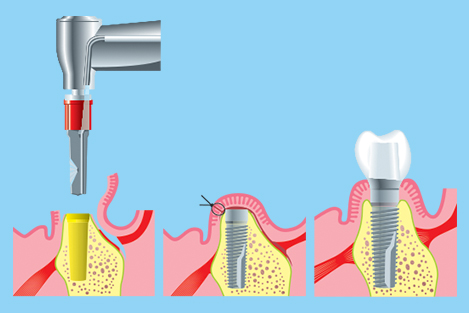

8. Dental implants

The primary use of dental implants are to support dental prosthetics. Modern dental implants make use of osseointegration, the biologic process where bone fuses tightly to the surface of specific materials such as titanium and some ceramics. The integration of implant and bone can support physical loads for decades without failure.